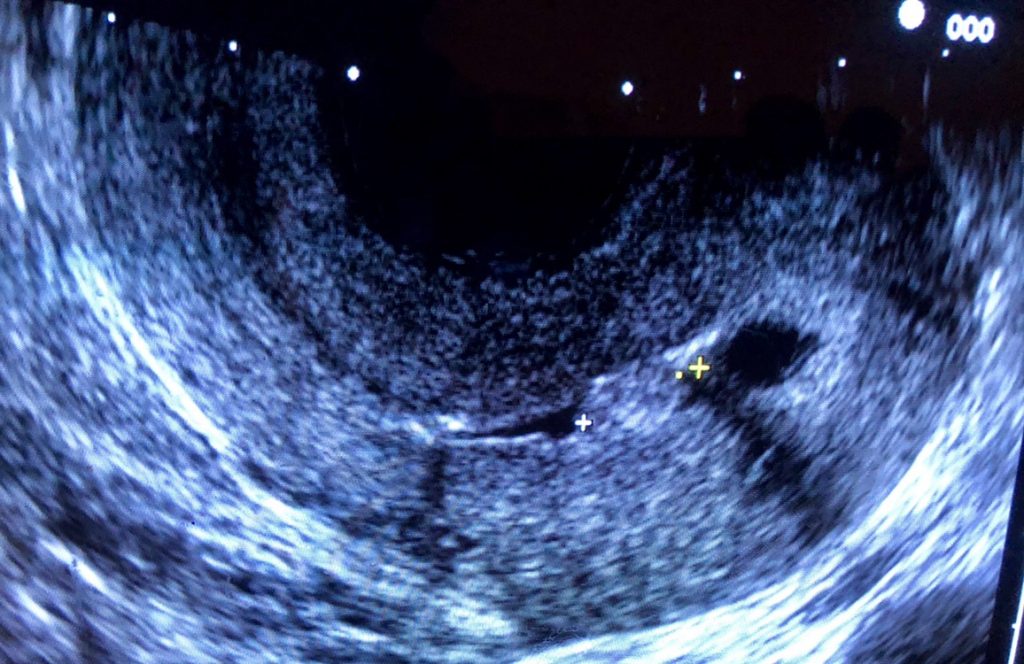

L’hystérosonographie est un examen échographique permettant de mieux explorer la cavité utérine qu’une échographie classique. Elle consiste à introduire du liquide physiologique à l’intérieur de l’utérus par un cathéter introduit par le col et à faire l’échographie pendant l’injection du liquide physiologique. La présence du liquide dans la cavité utérine va permettre ainsi une meilleure visibilité de la paroi et montrer d’éventuelles pathologies comme un polype ou un des adhérences…